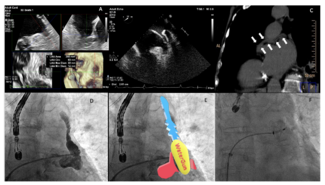

Raúl Moreno-Gómez, MD, PhD; Guillermo Galeote, MD, PhD; Santiago Jimenez-Valero, MD, PhD; Alfonso Jurado-Román, MD, PhD; Ariana Gonzalvez-Garcia, MD

This case represents the first patient with Mitraclip, Amplatzer, and TricValve devices with a profound clinical improvement and long-term follow-up.